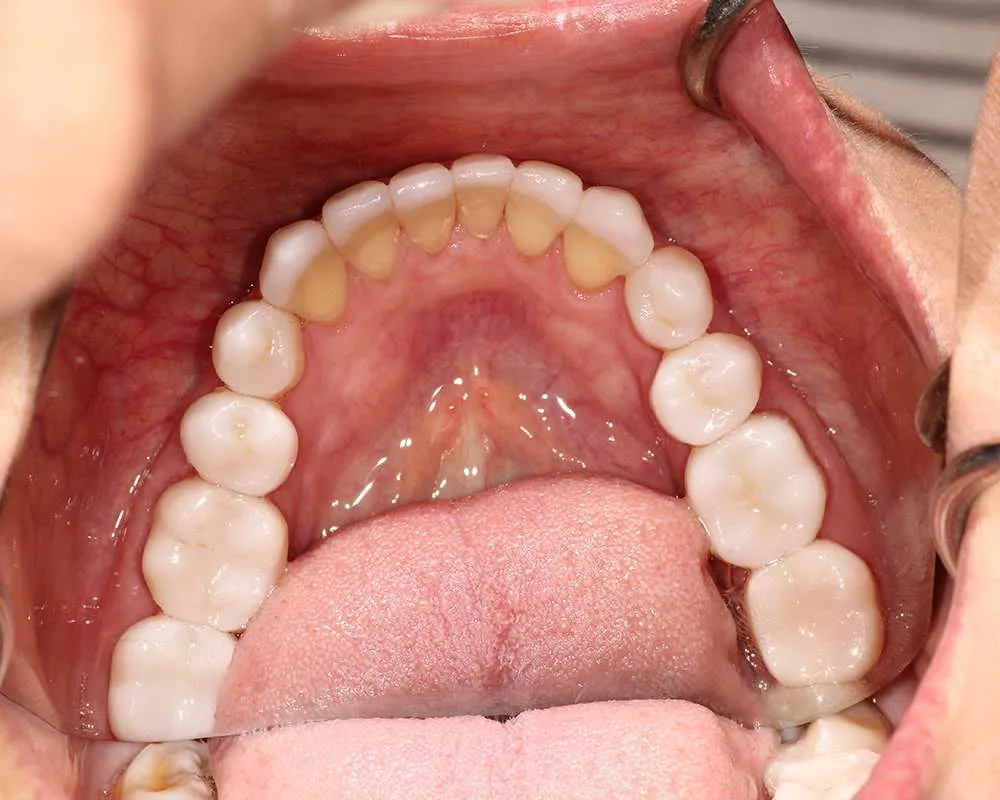

The process of getting ultra-thin veneers typically involves several steps. First, during the initial consultation, we will discuss your goals and take impressions and photographs of your teeth. Next, we will minimally prepare your teeth generally less than 0.5mm of preparation (sometimes little or no preparation is needed depending on the design). Then you'll leave with a 'trial smile' and temporary veneers in place, after which we'll have a follow-up appointment the next day for final evaluation of your temporary veneers for tweaks and fitting to help guide the lab to your custom smile. Your veneers are finally crafted in a premier dental lab. Finally you'll return to the office where your custom, ultra-thin veneers are bonded to your teeth using biocompatible materials. The entire process usually takes one to four weeks from start to finish depending on the lab and complexity of the case.